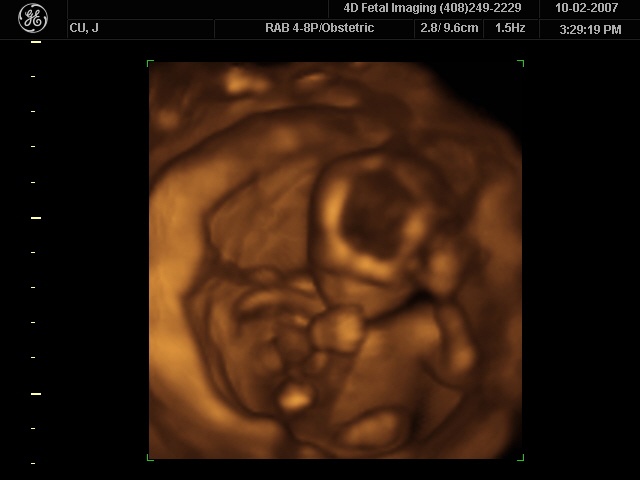

How much detail can ultrasound reveal? The image in this figure is typical of low-cost systems, but that in this figure shows the remarkable detail possible with more advanced systems, including 3D imaging. Ultrasound today is commonly used in prenatal care. Such imaging can be used to see if the fetus is developing at a normal rate, and help in the determination of serious problems early in the pregnancy. Ultrasound is also in wide use to image the chambers of the heart and the flow of blood within the beating heart, using the Doppler effect (echocardiology).